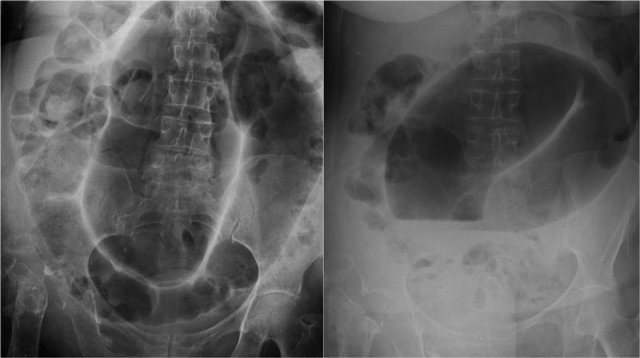

On the left there are additional CT-images of the same patient as above.

First look at these images and look for the major findings and then continue.

First we see a collapsed descending colon and a non-dilated ascending colon, so this cannot be a sigmoid volvulus.

Secondly, we see a beak-like structure in the right lower quadrant which is where the bowel is twisted.

In the left lower quadrant we see the dilated cecum.

Coronal recontructions can be very helpfull in demonstrating what is going on.

On the left we see the non-dilated ascending and descending colon (straight arrows) and the transition point of the volvulus (curved arrow).

Cecal volvulus is due to the cecum twisting around the ascending colon thus leading to small bowel obstruction.

On the left a patient with a sigmoid volvulus.

We can see the distended sigmoid extending from the pelvis way up into the right upper quadrant.

Look at the image and decide for yourself why this cannot be a cecal volvulus.

Then continue.

The key finding is the dilatation of the proximal colon.

The dilated loop seen on the left side is the dilated transverse colon.

At CT we can nicely appreciate the area of the twist with the sigmoid extending up to the diafragm.

AP supine and erect radiograph of the abdomen demonstrates the characteristic coffee bean sign in sigmoid volvulus.

Notice that the dilated loops point towards the sigmoid area.